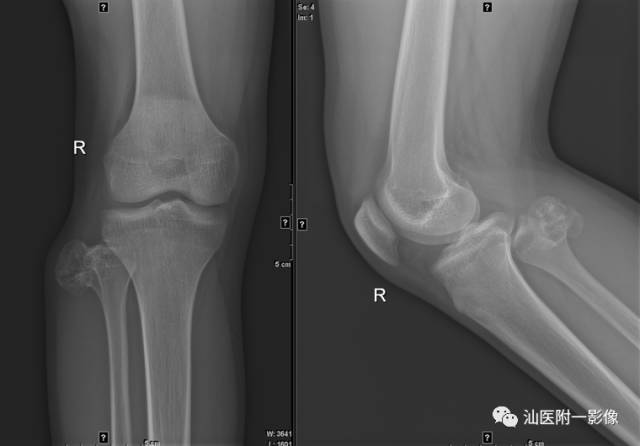

1.骨软骨瘤

•又称骨软骨性外生骨疣,特征为位于骨外表面的有软骨帽的骨性凸起。

•最常见的良性骨肿瘤(20-25%)。10-30岁多见。

•好发于长骨的干骺端(膝关节周围、肱骨近端)。

•病理:骨性基底+软骨帽+纤维包膜。